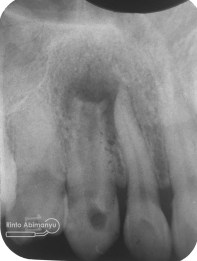

Pemeriksaan respon dingin pun menunjukkan hasil negatif, untuk menambah data dalam penegakan diagnosis maka dilakukan pengambilan ronsen pada gigi2 tersebut

Terlihat dari ronsen tersebut karies pada gigi 23 24 sudah mencapai pulpa… dari informasi pemeriksaan klinis dan ronsen maka didiagnosis gigi tersebut nekrosis.. Saya jelaskan kepada pasien mengenai kondisi gigi2 nya dan rencana perawatan yang akan saya lakukan…